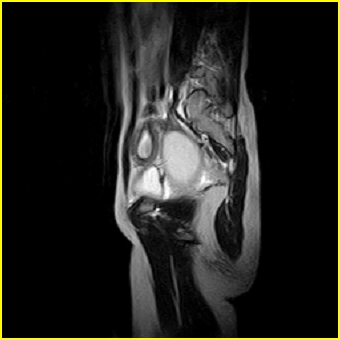

女、15岁、下腹疼痛2天,排尿困难1天。查体:处女膜闭锁,距处女膜约4至5cm处扪及一约5cm直径的圆形包块,张力较高,触痛明显、欠活动。b超提示子宫增大伴宫内增强回声团。

影像意见:子宫直肠陷凹积血。

更正影像意见:阴道积血。

处女膜闭锁,阴道积血

处女膜闭锁,阴道积血,子宫积血.

阴道积血,子宫积血.

子宫及阴道积血。

处女膜闭锁,伴子宫及阴道积血.